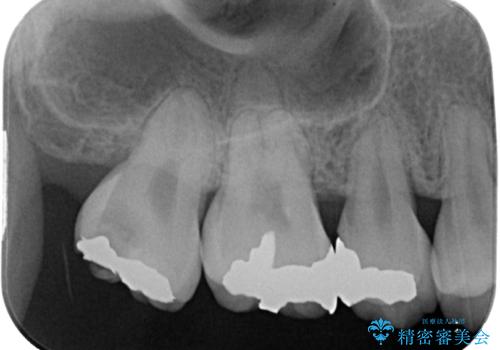

セラミッククラウンの適合はレントゲン写真からも分かる通り、境界がぴったりと合った、高適合のものとなりました。